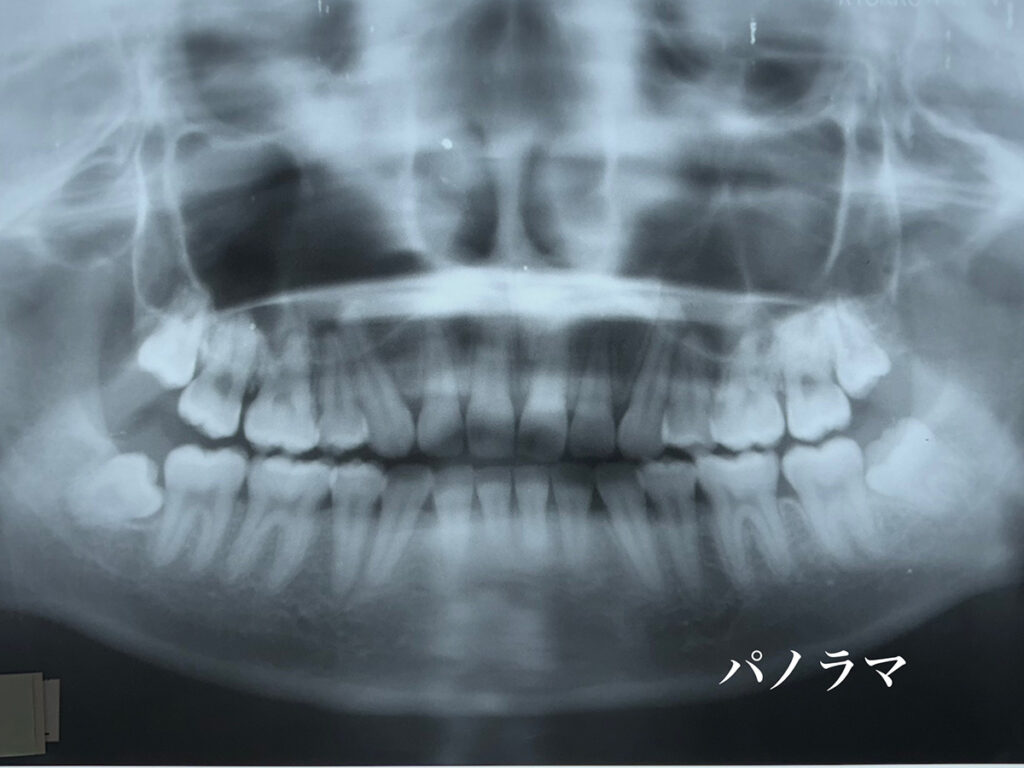

レントゲン所見においては、矯正歯科治療においてセファロ写真分析は欠かせません。

しかし、それだけでは情報量としては不足だと考えています。

私はレントゲンメーカーの協力によって特注の機器を製作していただき臨床に活用しております。頭蓋骨の3軸方向からの分析し、骨の変形とともに、頭蓋骨と下顎骨との位置的関係について精査し、正しい咬み合わせでの歯科矯正治療を確実に行います。

一般的な歯科矯正治療の資料である、患者さんの口腔内写真、顔貌写真も、もちろん活用して診断の一助としています。